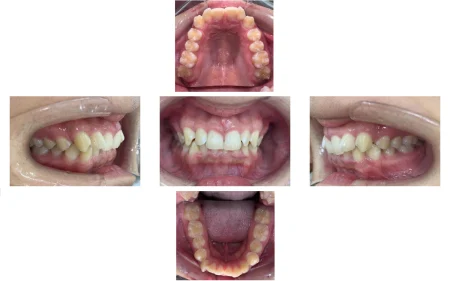

拝見したところ、噛み合わせた時に上の前歯が覆いかぶさり、下の前歯がほとんど見えないほど噛み合わせが深い「過蓋咬合(かがいこうごう)」が認められました。

また、上左右の前歯(側切歯/2番)と右下の前歯(犬歯/3番)は、捻れて生える「捻転(ねんてん)」が見られました。